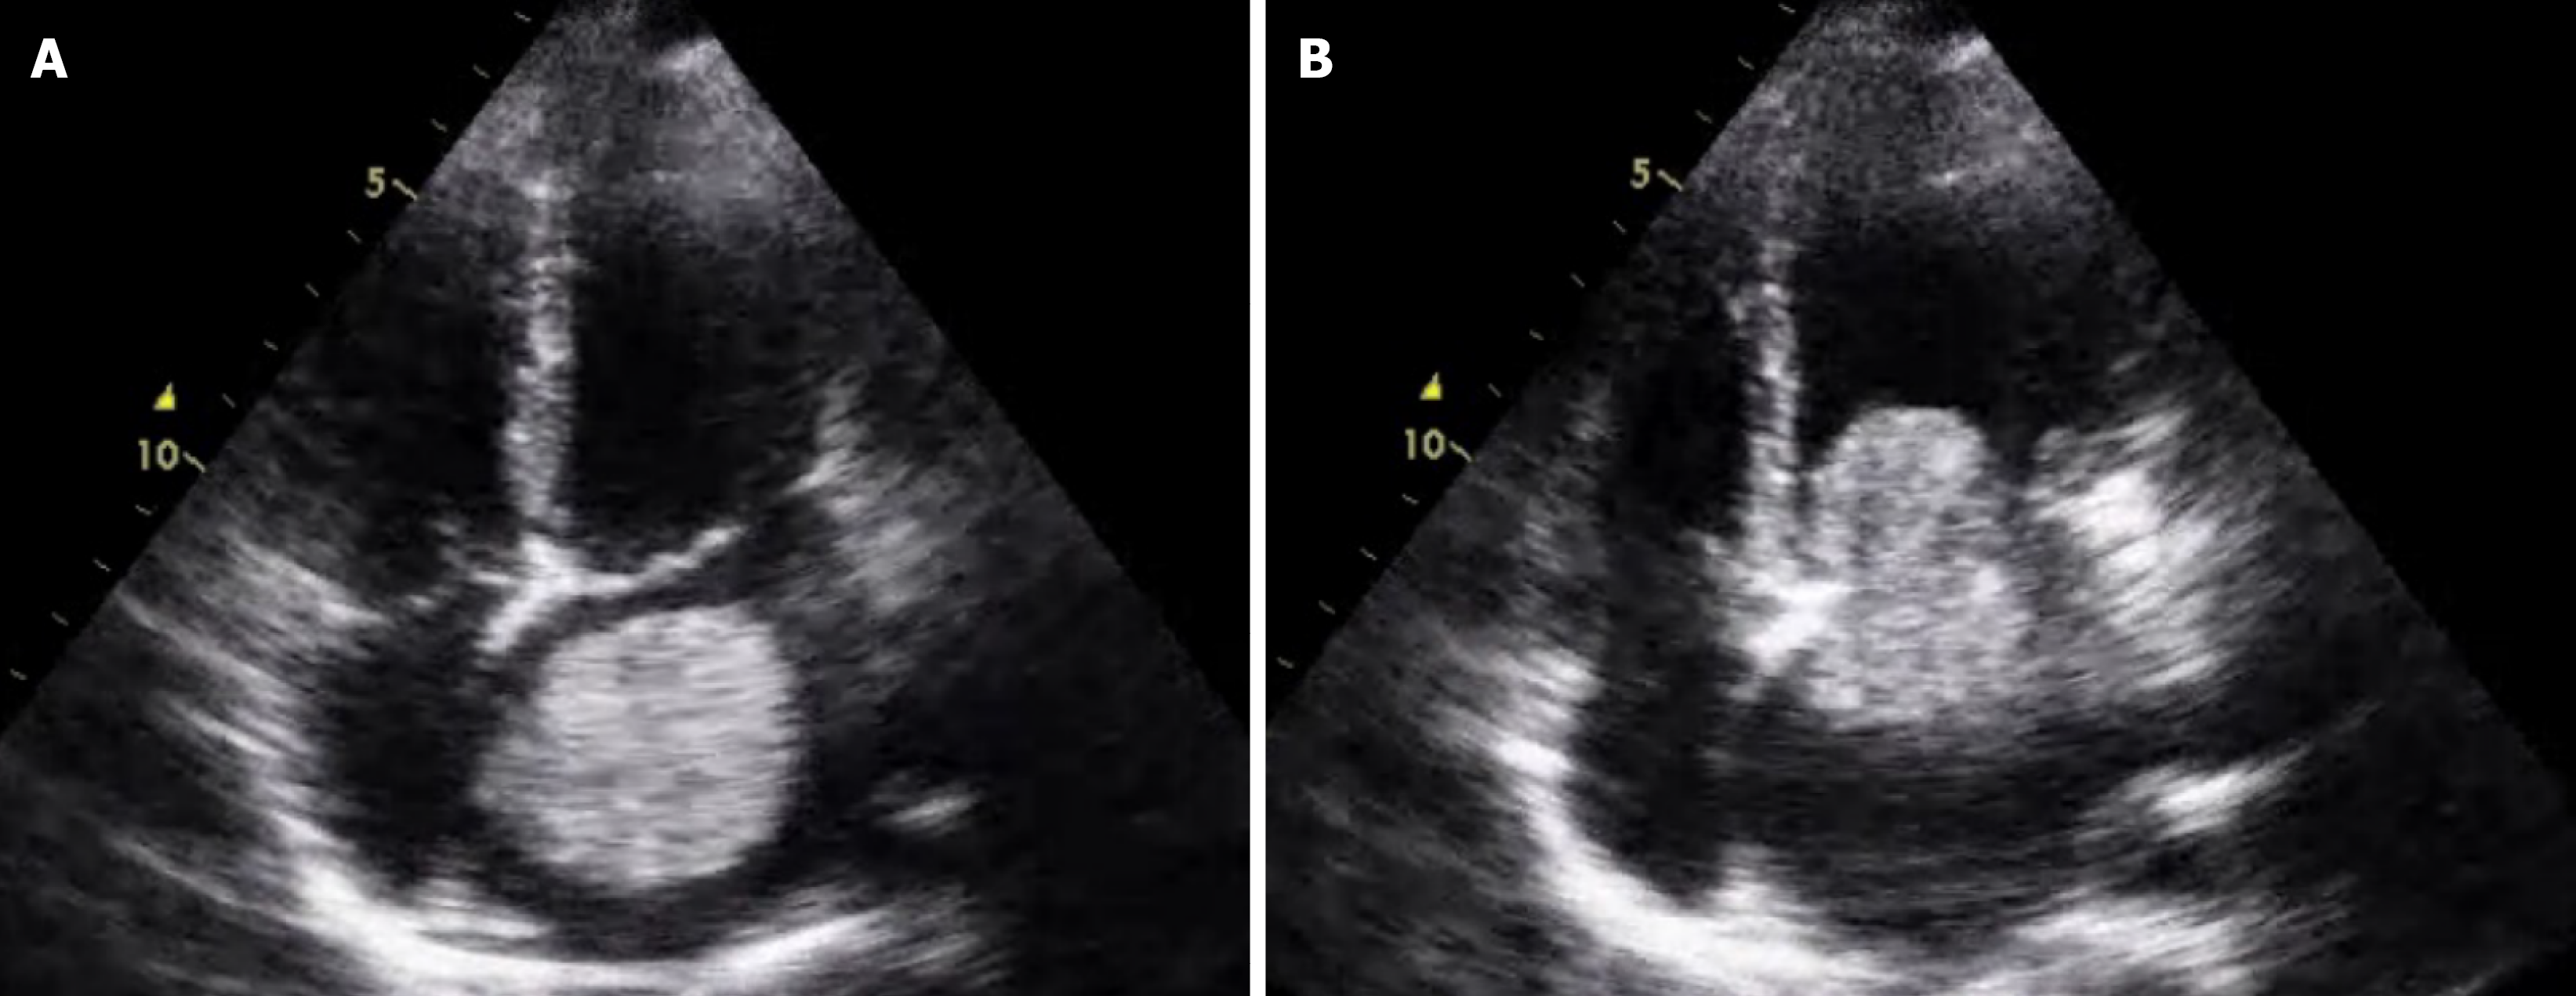

Figure 1 Transesophageal echocardiographic findings of left atrial mass.

A: Round mass was visualized in the left atrium, confined within the left atrium during systole; B: The mass extended into the left ventricle during diastole.